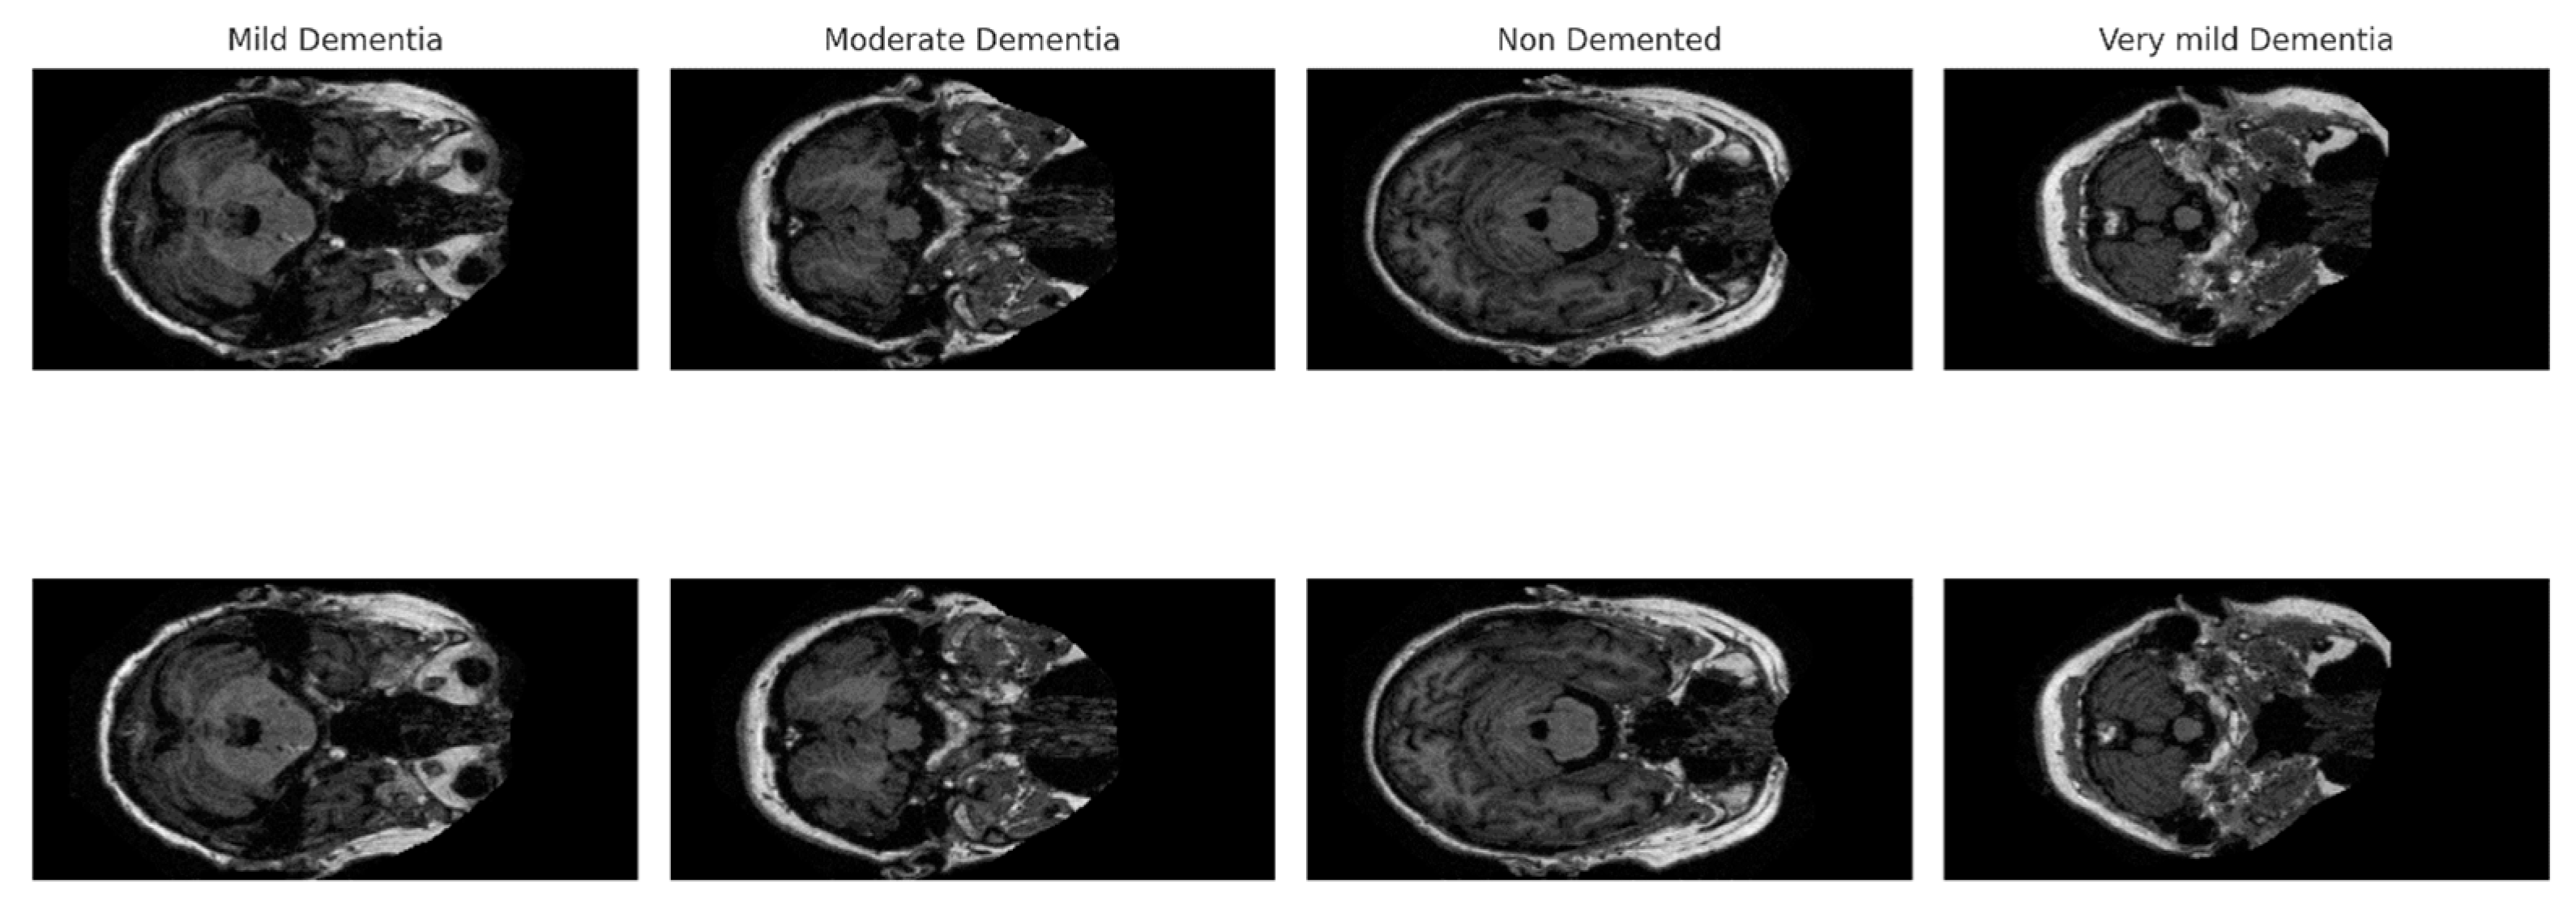

The OASIS (Open Access Series of Imaging Studies) dataset published on the Kaggle platform [33] is used in the study. There are four classes in the dataset classified according to the progression of Alzheimer’s disease [33].

• Non-Demented (ND): Healthy individuals without a diagnosis of dementia.

• Very Mild Demented (VMD): Very mild dementia.

• Mild Demented (MD): Mild dementia.

• Moderate Demented (MoD): Moderate dementia.

The dataset contains a total of 9488 brain MRI images. The primary purpose of this dataset, which includes images from individuals of various age groups and clinical conditions, is to analyze and identify early signs of Alzheimer’s disease. Figure 3 presents sample images from the dataset, randomly selected from each class.

Figure 3. Example images of classes in the OASIS MRI dataset.